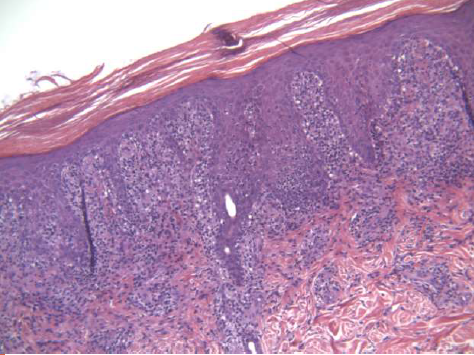

What is the differential when you see psoriasiform dermatitis?

A

• Clear cell acanthoma

• Chronic spongiotic dermatitis

• Pityriasis rosea (less likely)

• Lichen simplex chronicus

• Mycosis Fungoides

• FUNGAL DISEASE(s) – TINEA!!

If you are shown this pattern of a lichenoid infiltrate WITH psoriasiform hyperplasia, what ONE entity should you think about?

SYPHILLIS